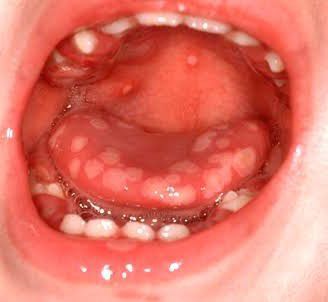

Gingivostomatitis is a highly contagious infection of the mouth caused by Herpes Simplex Virus type I (HSV-I).It is common in children between the age of 6 months to 5 years but also seen in adults. The treatment goal is to reduce the discomfort and pain associated with the disease. Credits: https://images.app.goo.gl/ipJDpTQeBs9LXKKQ9